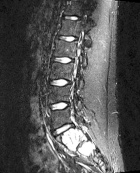

20 year old male with a six month history of low back and buttock pain

Zoom image: Radiological image Radiological image.